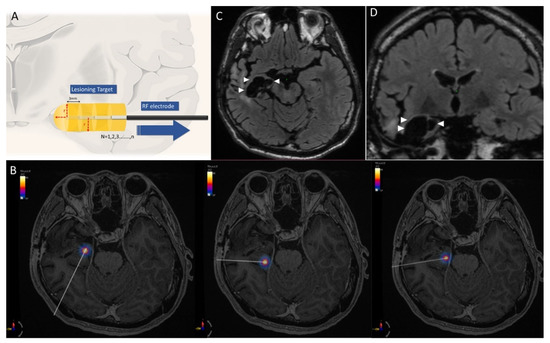

3.2. Case 1. Right Temporal Seizure after ATL

| 1 | Male | 28 | Right hippocampal sclerosis | Partial anterior temporal lobectomy | Right remanent hippocampus | 3 | 9949.69 | 9727 (2.3%) | 1 | 2 | none | 1a |